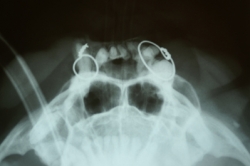

- Radiográfico (analógico y digital)

El diagnóstico clínico oral es de suma importancia ya que el plan de tratamiento y el pronóstico dependen de un certero y profundo análisis de los signos de la cavidad oral. Nuestra principal preocupación es atender los problemas que se encuentran en cavidad oral pero además siempre realizamos un detallado análisis de la función general del paciente. En nuestro centro revisamos de manera general a la mascota detectando cualquier problema sistémico. Contamos con un laboratorio de análisis clínicos en donde se realizan biometría hemática, química sanguínea, examen general de orina y pruebas para detección de enfermedades virales y de otros microorganismos. Contamos también con un laboratorio de histopatología en donde se revisa el material biológico para la detección y el diagnóstico de cambios morfológicos y lesiones en los tejidos. En lo que respecta al diagnóstico de la boca, contamos con un expediente donde se vacía toda la información dental y bucal de tal manera que mantenemos el control del tratamiento odontológico desde el inicio hasta el final y en donde el propietario o el médico que nos recomienda puede revisar en detalle toda la información recabada. Contamos con todo el instrumental y el equipo necesario para el diagnóstico de el aparato estomatognático (cavidad oral con dientes, tejidos de sostén y tejidos blandos, además de las estructuras relacionadas como articulación temporomandibular, cavidad nasal, cavidad orbitaria, etc.). Contamos con luz similar a la ultravioleta para diagnóstico de lesiones dentales por transluminación, pulpómetro para diagnóstico de vitalidad pulpar, localizador de ápices para tratamiento de conductos y equipo radiográfico tanto analógico como digital.